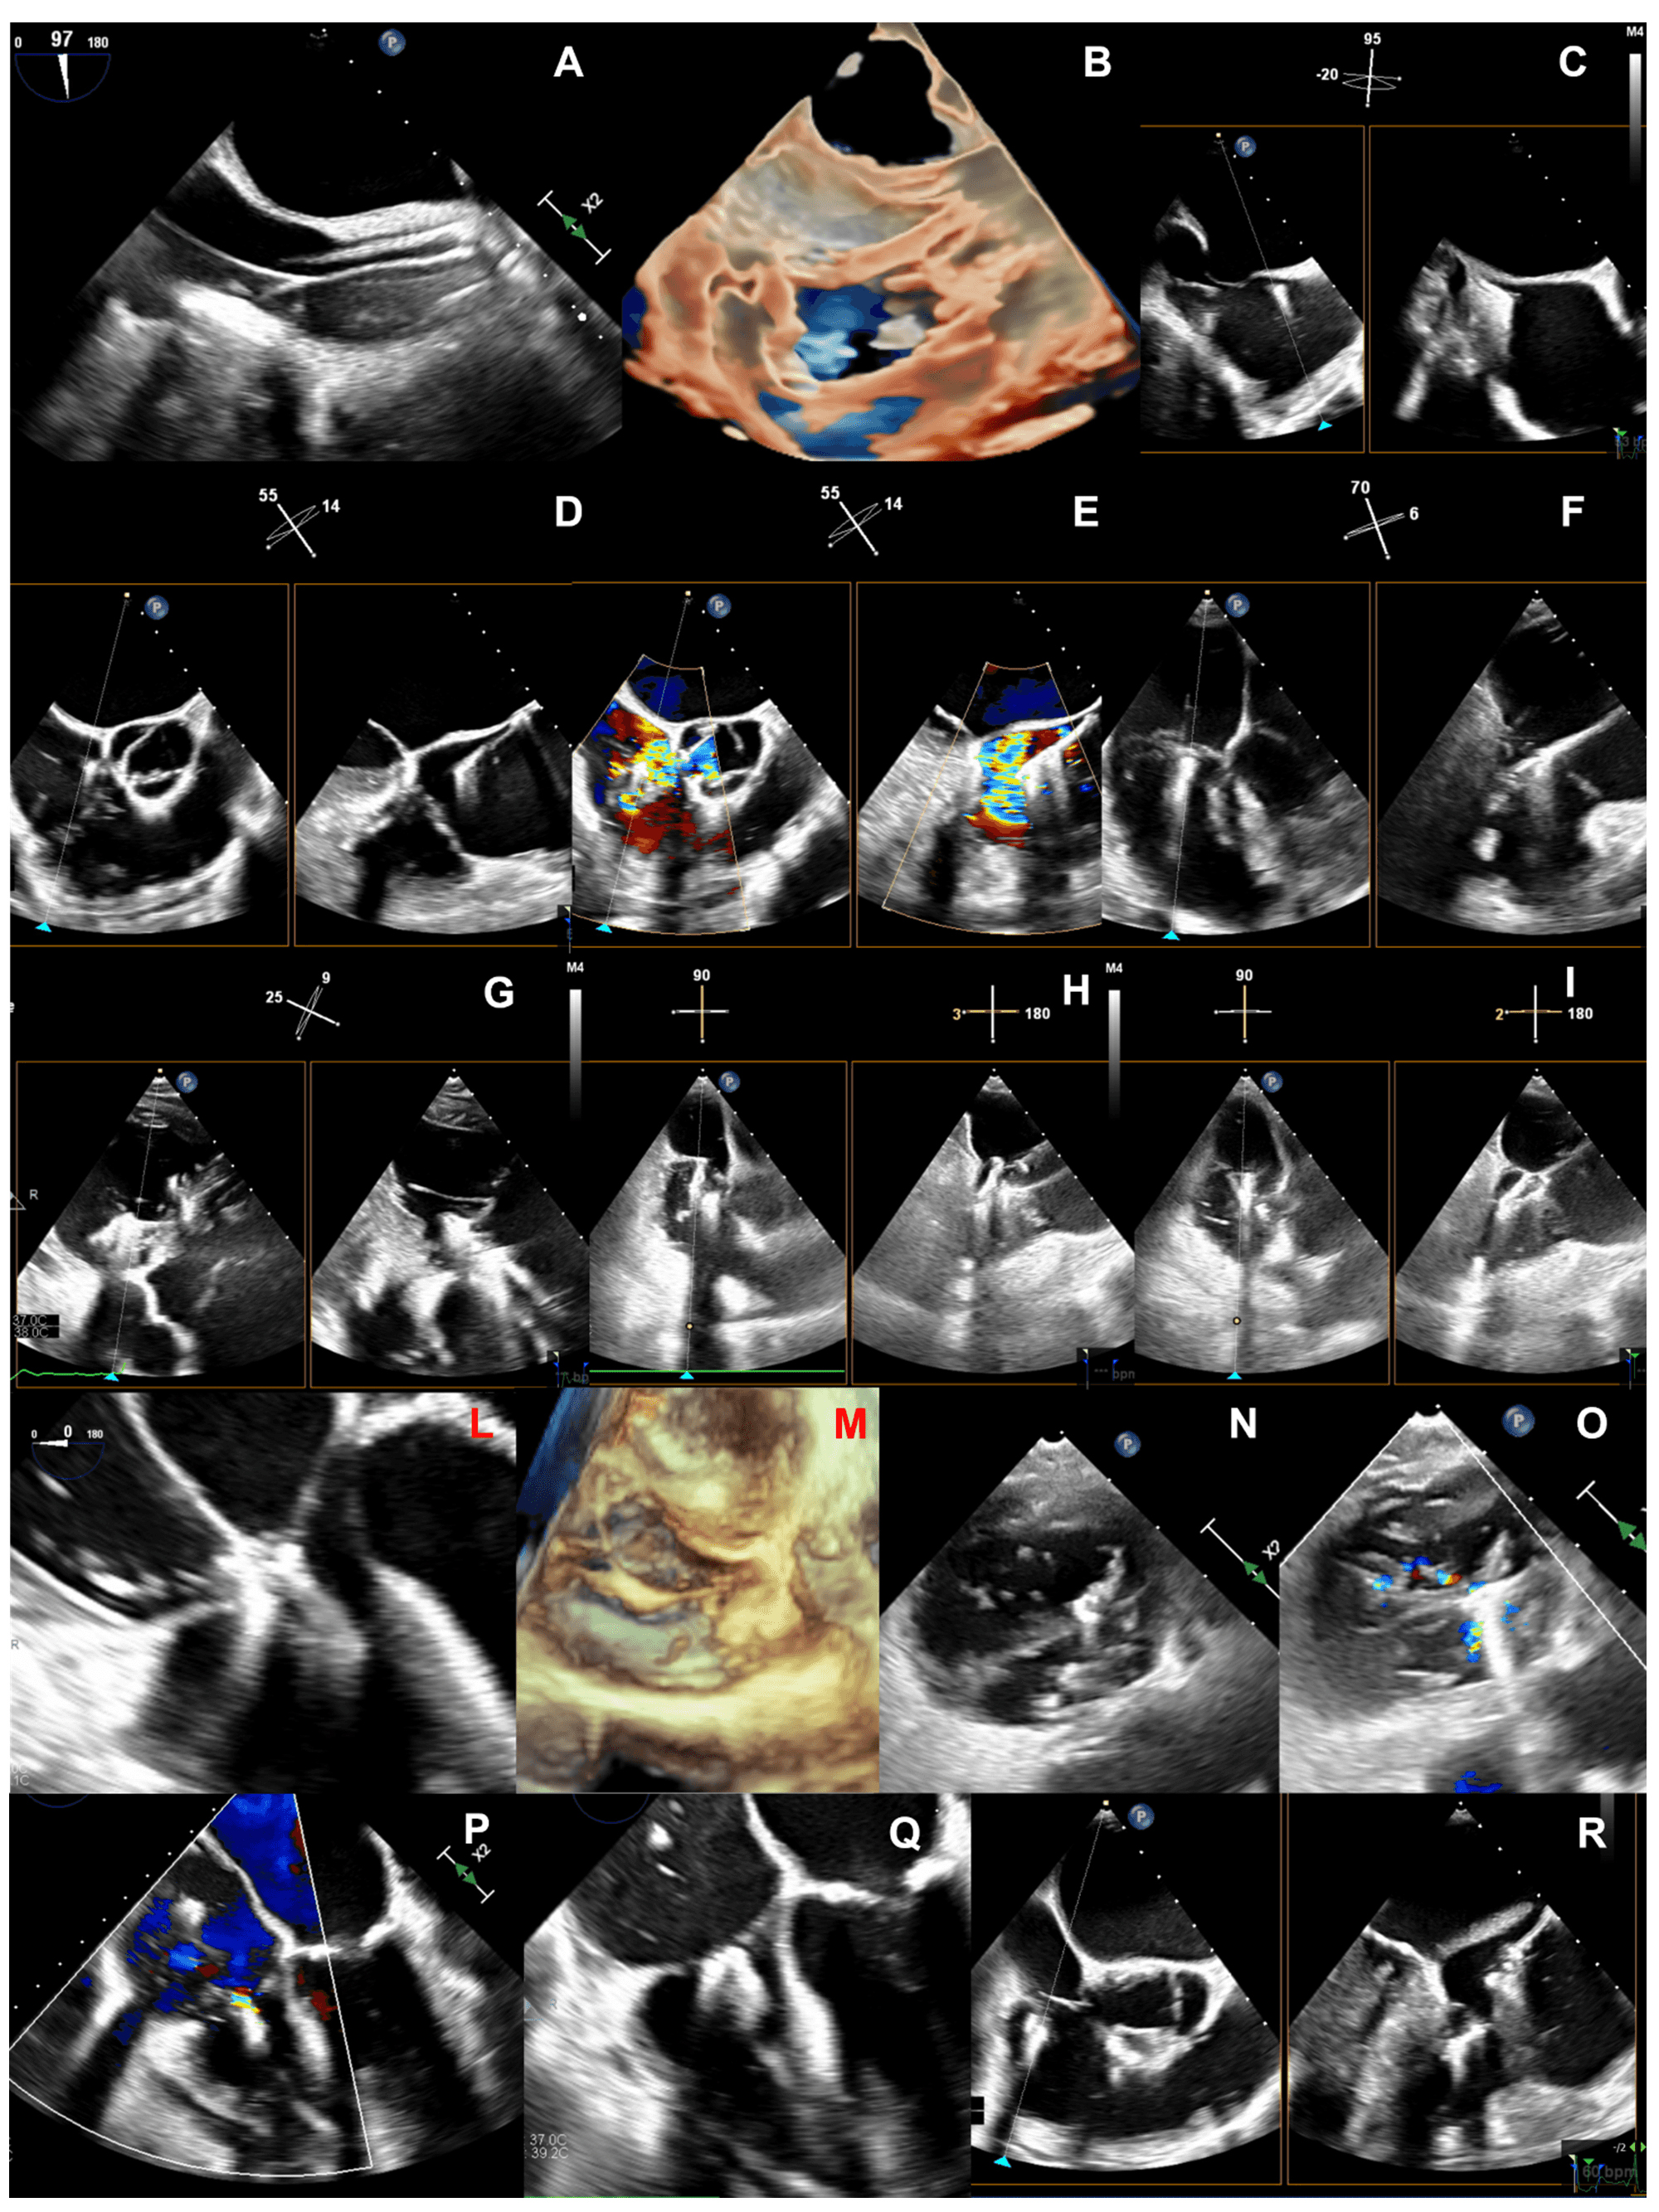

Due to its complex nature, the assessment of TV morphology and disease mechanism requires multiple TTE and TEE windows [2].

The main TTE views are the left parasternal long-axis (LAX) view focused on the RV inflow, the left parasternal short-axis (SAX), the apical and the subcostal views (Table 1). The visualization of all leaflets in one two-dimensional (2D) view is only rarely achieved, mainly through modified subcostal or parasternal SAX windows. A precise TTE characterization of the leaflets is challenging but few anatomic landmarks may be helpful to guide the imager (Table 1) [2, 36, 37]. The aortic valve permits to localize the anterior leaflet, in particular the non-coronary cusp is adjacent to the antero-septal commissure. The entry point of coronary sinus into the right atrium (RA) locates the postero-septal commissure, instead.

|

| Abbreviations: AL, anterior leaflet; LVOT, left ventricular outflow tract; PL, posterior leaflet; PLAX, parasternal long-axis; PSAX, parasternal short-axis; SL, septal leaflet; TV, tricuspid valve; Var., variable. |